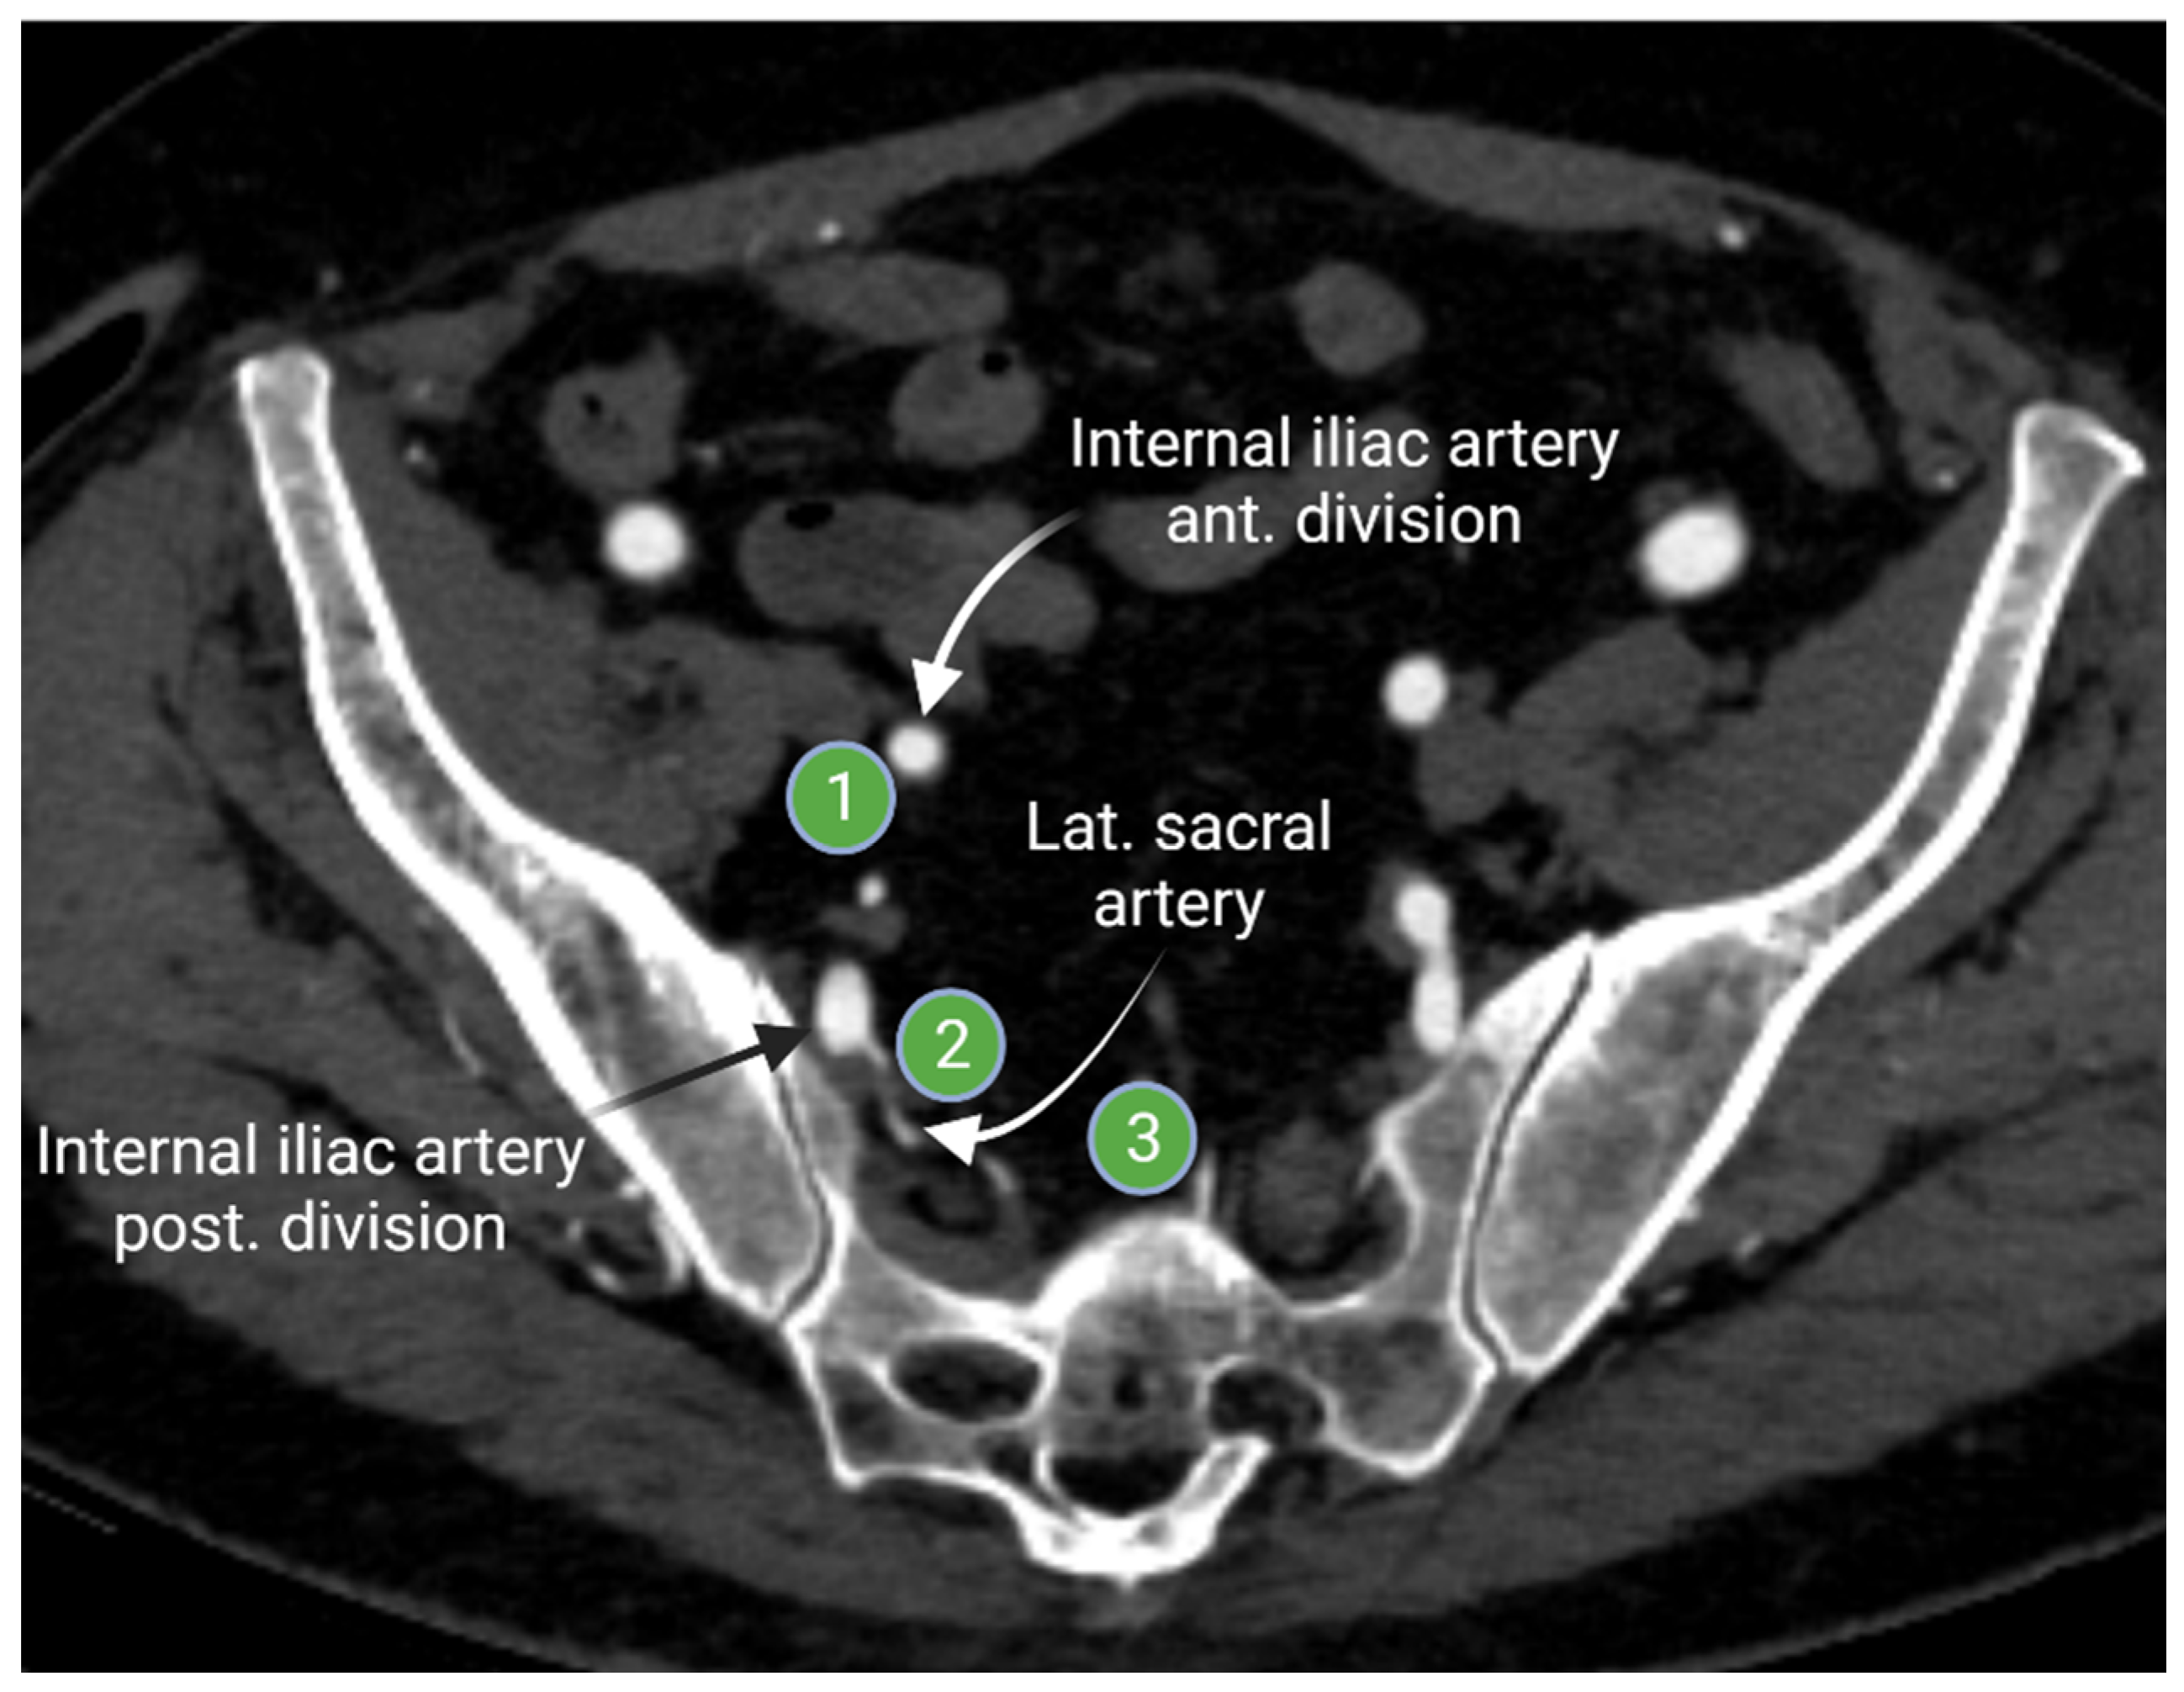

2.1.2. Iliac Lymph Nodes Anatomy